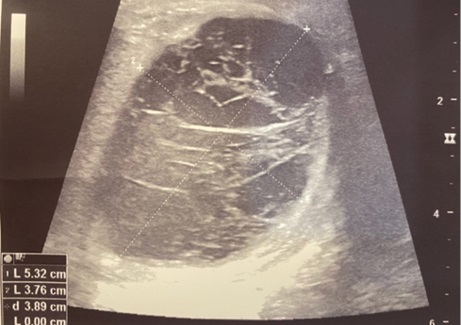

В пяти случаях из семи — 71,4 % — хирургическая находка соответствовала результатам ультразвукового исследования, что подтверждается следующими клиническими иллюстрациями (рис. 2, рис. 3).

Рис. 2. А. Неоднородность нижнего полюса яичка и придатка (УЗИ в горизонтальном срезе)

Рис. 2. Б. Отрыв хвоста придатка в области нижнего полюса яичка

Рис. 2. Больной М, 15 лет. 12 часов после травмы — удар ногой в промежность снизу верх